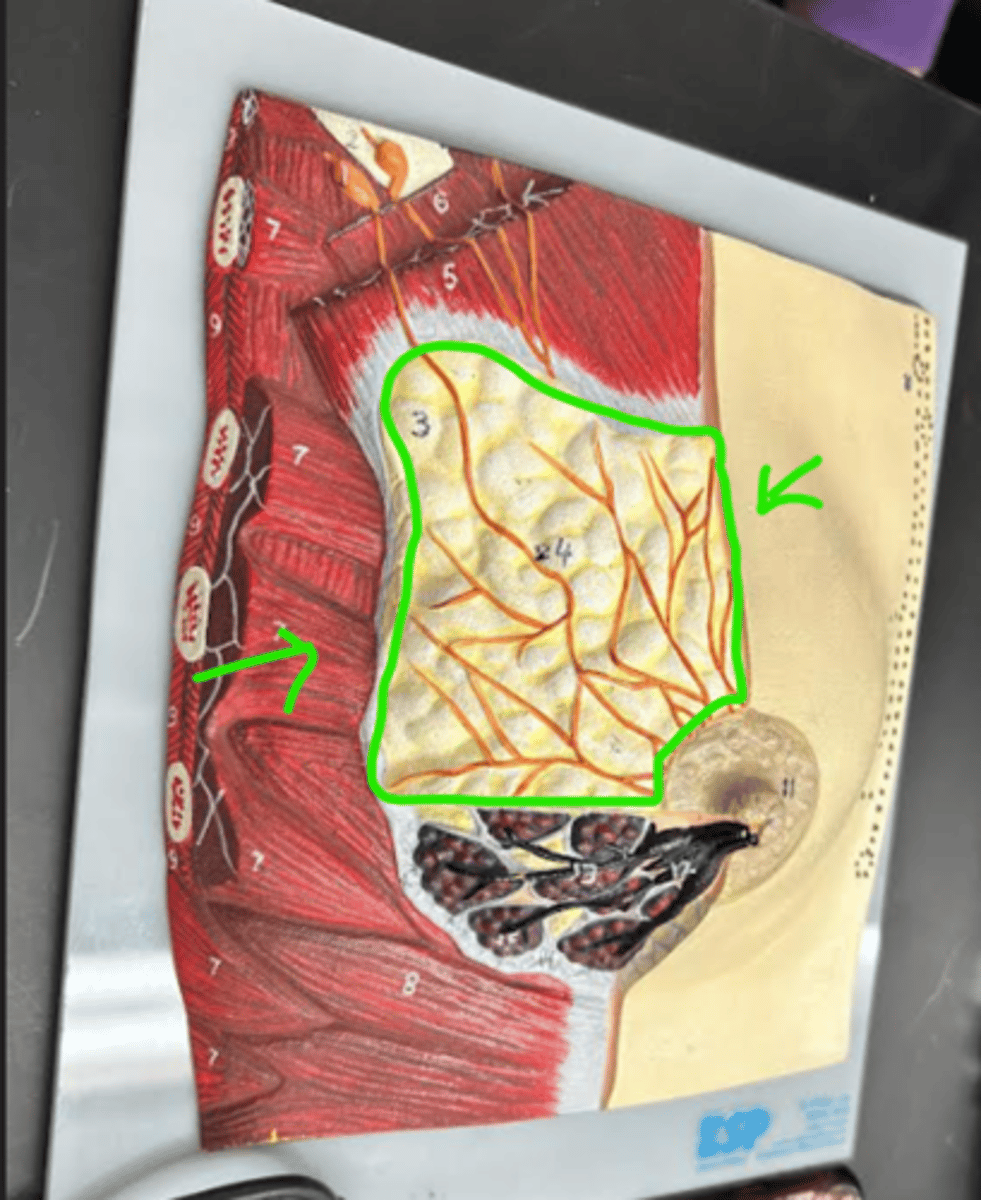

Breast

whole structure/ model

Axillary tail

Areola

Nipple

Suspensory ligament

Adipose tissue

Lactiferous sinus

Lactiferous duct

Mammary lobe

Mammary lobule